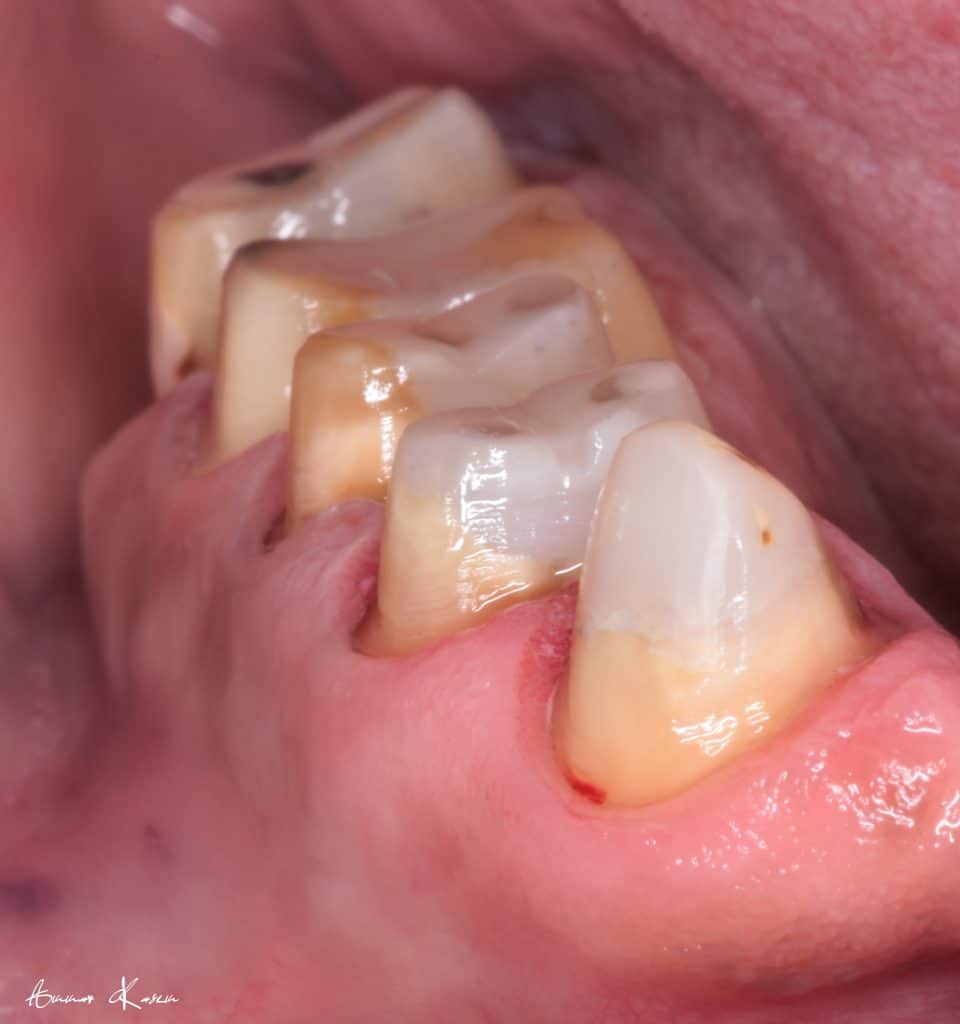

7- Preparation phase through half arch technique to preserve the vertical dimension

8- Ceramic fabrication including zirconia bridge and e.max crowns